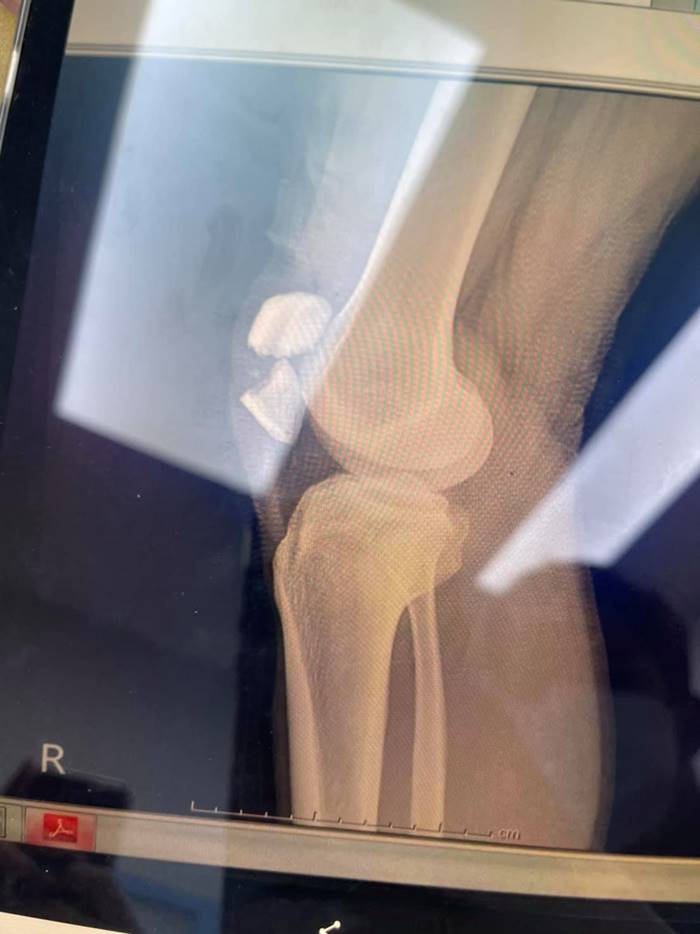

อย่างไรก็ดี จากที่ตอนแรกคิดว่าหัวเข่าแค่หลุด แต่พอเอกซเรย์ดูแล้วพบว่าสะบ้าแตก เหมือนโดนรถชนกระแทกอย่างแรง จึงต้องผ่าตัดทำเรื่องส่งไปรักษากับอีกโรงพยาบาลที่สะดวก คุยเรื่องค่าใช้จ่ายในการรักษาแล้วอยู่ที่ 360,000 บาท เบื้องต้นเมื่อผ่าตัดเสร็จก็จะต้องเหยียดขาตรงไปสักระยะ หลังจากนั้นก็ทำกายภาพ ต้องคอยขยับให้เลือดหมุนเวียน ใช้เวลาฟื้นตัว 3-6 เดือน และสภาพของเข่าคงไม่ดีเหมือนเดิม